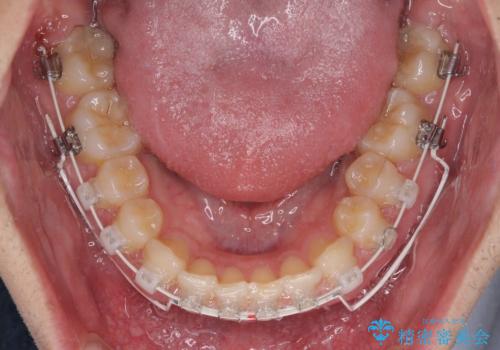

- 矯正装置

- 審美装置

アンカースクリューを用いて下に位置している上顎前歯を持ち上げるとともに、ワイヤー装置によりディープバイトの原因である奥歯の傾斜を改善することで、矯正治療を行っていくこととしました。

また、矯正治療に際し、4本全ての親知らずと、埋もれている右上小臼歯を事前に抜去することとしました。